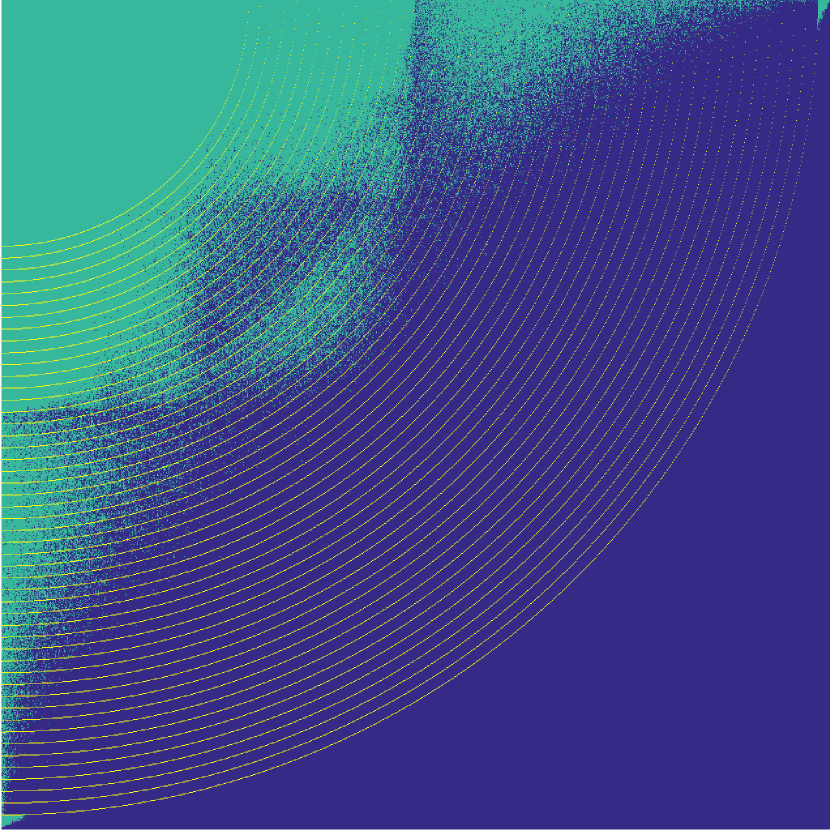

Figure 7 illustrates the best-performing randomized indices vs. our learned set of indices in the -space along the and directions. When optimized for the linear decoder, the indices of [3, 4] concentrate on low frequencies. While our strategies based on optimizing and (again using ) also do this to some extent, there is a stark contrast in the shape, since we do not restrict ourselves to patterns exhibiting circular symmetry.